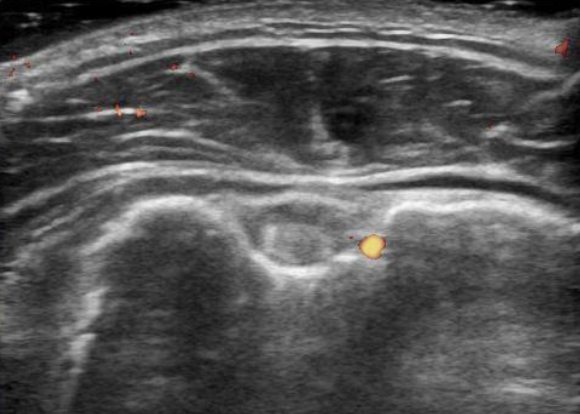

超音波検査について

リウマチ科領域では超音波診断の有用性が認識され、日常診療でも広く普及しつつあります。リウマチ性多発筋痛症においても超音波検査を用いた診断を実践していますが、多くの画像所見は特徴的ではあっても疾患特異的(すなわち確定診断の根拠となる)所見ではないため、症状を有する部位の観察のみで診断が得られることはまずありません。

他の疾患を正しく鑑別するためには、

- 症状を有する部位以外の画像所見の評価

- 他の臨床情報も十分加味

- 必要に応じて関節穿刺を行い貯留した液体の評価